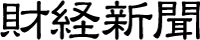

さらに本研究は、[⁶⁴Cu]Cu-ATSM を用いることで“低酸素領域の可視化(診断)”と“局所放射線治療(治療)”を単一薬剤で実現する診断・治療一体型(セラノスティクス)アプローチを実証・確立しました(図1)。

図1 [⁶⁴Cu]Cu-ATSMを用いたセラノスティックスアプローチの概要図